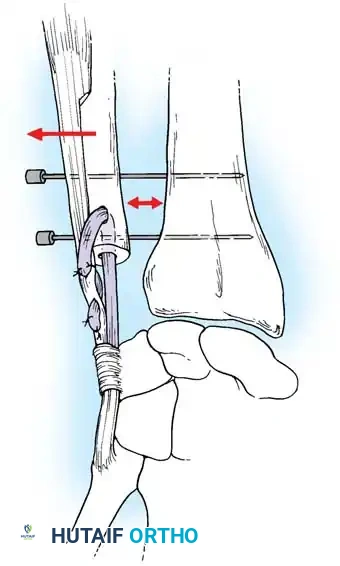

Preparation of the distal ulna: Drill holes are created at the fovea to facilitate transosseous suture passage for anatomic TFCC reattachment.

Transosseous Repair Technique:

1. Identify the foveal detachment arthroscopically or via an open dorsal ulnar approach.

2. Prepare the ulnar fovea down to bleeding bone using a burr or curette to stimulate a healing response.

3. Utilize a targeting guide to drill two converging osseous tunnels from the ulnar neck into the fovea.

Passing non-absorbable sutures through the osseous tunnels in the ulna to capture the peripheral edge of the TFCC.

- Pass strong, non-absorbable sutures (e.g., 2-0 FiberWire) through the TFCC using an outside-in or inside-out technique, then shuttle the suture limbs down the osseous tunnels.

The sutures are tied securely over the cortical bone bridge of the ulnar neck, restoring tension to the radioulnar ligaments.

- Tie the sutures over the ulnar cortical bridge with the forearm in neutral rotation to restore anatomic tension.